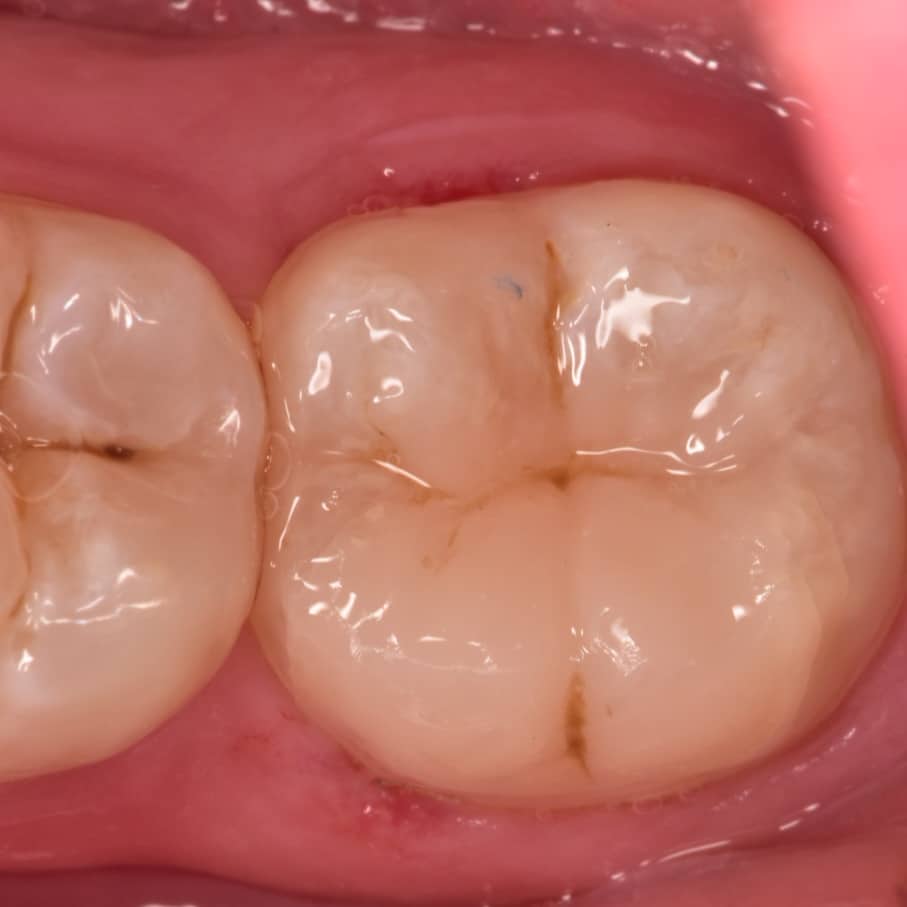

Occlusal view

Final result

Try to mimic the nature as could as possible